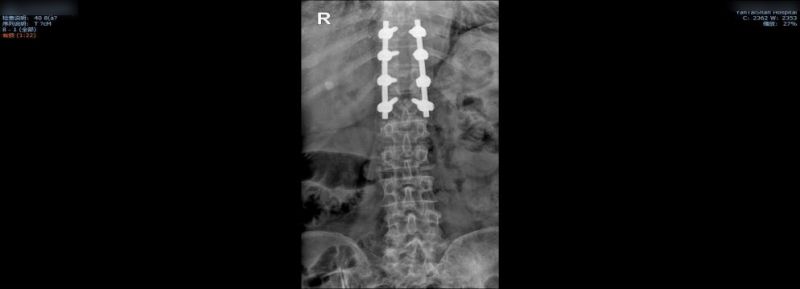

有了充分的术前准备,当天的手术在4小时之内完成,术中的出血量非常小,患者4个节段的胸椎管得以减压固定。术后第4天,她就可以下地活动。在此期间,病房护理人员也给予王阿姨无微不至的关怀,确保了术后安全,并帮她得以早日康复。